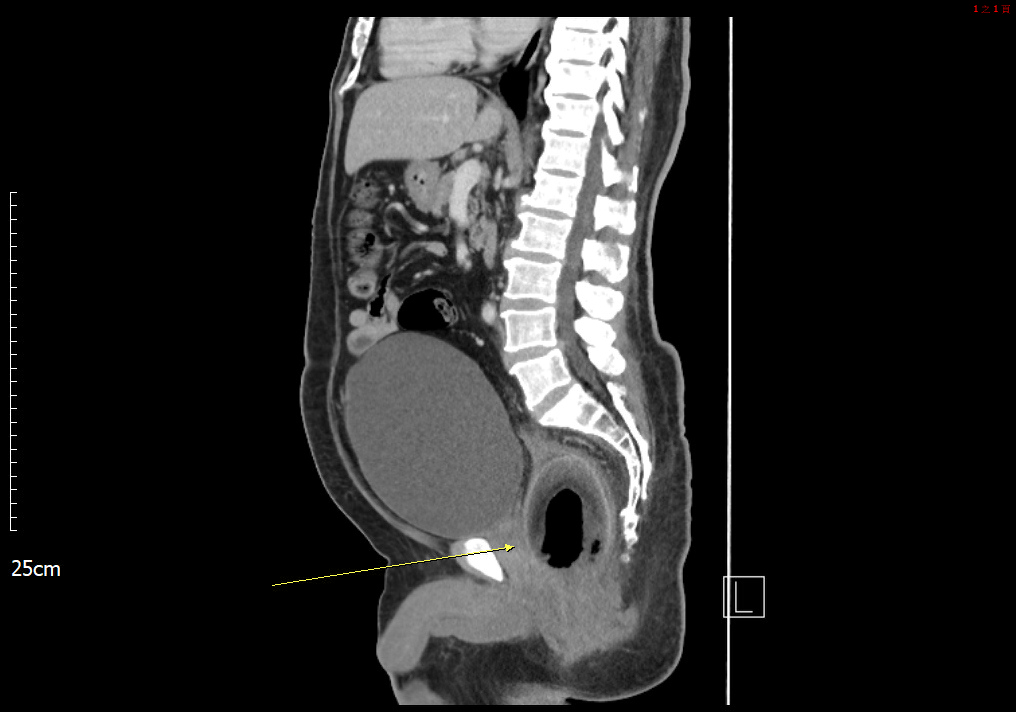

根據媒體《中時新聞網》、《ETtoday新聞雲》的報導,高雄一名50多歲的男子因為劇烈腹痛到義大醫院掛急診,稱自己已經肚子痛了2天,不僅便祕還小便上不出來。醫生細問後,男子坦承2天前曾塞東西進菊花,進一步安排電腦斷層掃描,醫生果然在他直腸發現一顆巨型圓狀物,因為壓迫到尿道才導致無法正常排泄。

由於男子膀胱約有2000c.c.的尿液無法排出,膀胱腫得像顆橄欖球,再拖下去恐有膀胱破裂、直腸壞死的風險,因此院方緊急安排剖腹手術,最後從男子的直腸取出一顆直徑為7.5公分椰子。男子事後坦承是想尋求刺激才會塞進椰子,這起荒謬病例甚至登上《英國醫學期刊》,不過男子究竟是怎麼塞進這顆龐然大物,他並沒有透露。